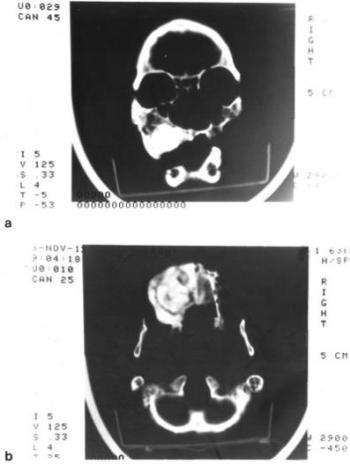

Az osteoid osteoma mindig jól körülhatárolt, többnyire a csontkéregben, ritkábban a szivacsos állományban helyezkedik el. Jellegzetes rtg-képe alapján könnyen megállapítható a helyes kórisme. A tumort osteoid szövet burjánzása képezi, amely a későbbiekben elmeszesedhet, s ezzel a klinikai tünetek (erős fájdalom) is csökkennek. Saját észlelésünk a rutinszerű röntgenvizsgálataink melléklelete. A fiatal férfi jobb tibiajának distalis metaphysisében, a szivacsos állományban 8 mm átmérőjű (60. ábra), jól körülhatárolt elcsontosodott, homogén szerkezetű daganatot figyeltünk meg. Napjainkban az osteoid osteoma gyakori, az őskórtani anyagban alig néhány eset leírása található (Gladykowska – Rzeczycka 1982,1985, Wyhnanek 1971).

60. ábra. a) A rutinszerűen végzett rtg-vizsgálatkor „mellékleletként” talált körülirt, intraossealis elváltozás (nyíl) a tibiában. b) A felfűrészelt tibia distalis metaphysisében 8 mm átmérőjű csonttumor (nyíl) helyezkedett el. c) A jól körülhatárolt, elmeszesedett osteoid osteomát dús trabecularis csonthálózat veszi körül. Sztereómikroszkópos felvétel 20× nagyítás. 9–10. század, adultus férfi